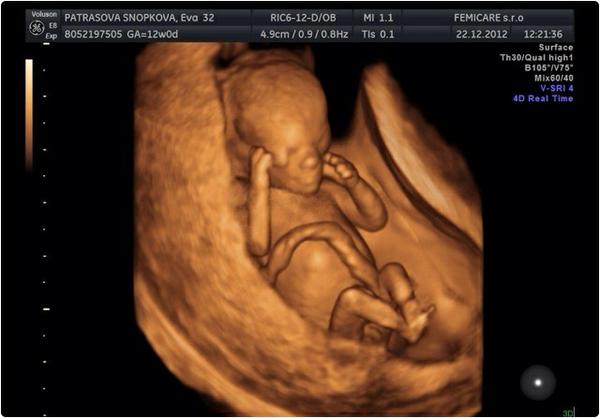

k kocky dodatocne prajem krasne sviatky boli aj krasne // vianoce @kikaneu tak gratulujem a pridavam foto nasho chlapceka

@michaelamia1902 krasne fotecky, vyzera akoby mal polmetra.. len ako viete,ze chlapec? 😉

@michaelamia1902 gratulujem k synčekovi. su to nádherné zábery. to kde robia takéto?

@michaelamia1902 krásne bábätko, gratulujem 😵 vidím tam tie jeho rozmery, že do 5 cm, a vyzerá ako veľký 🙂